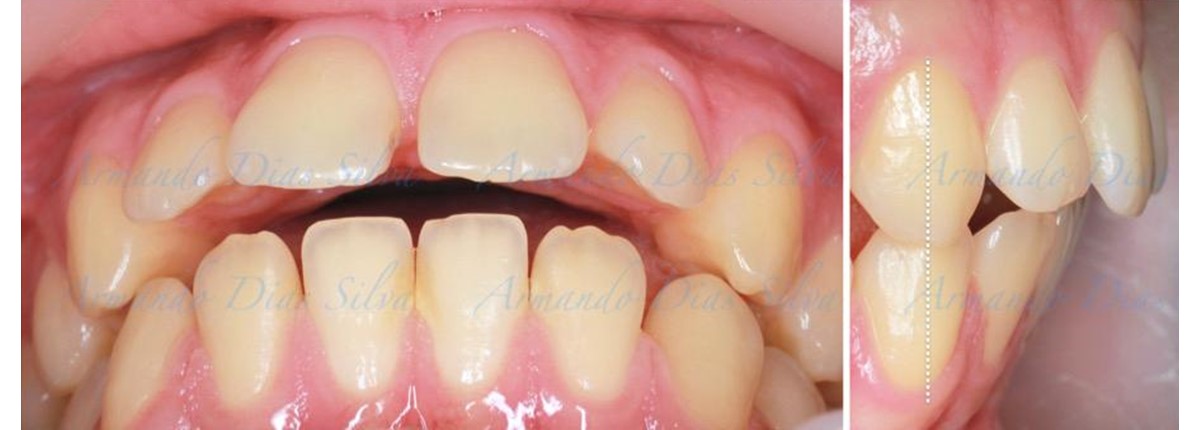

• Molares de clase II

• Diastema

• Espaciamiento leve de las arcadas superior e inferior (deficiencia transversal de 3,45 mm)

• El primer molar superior derecho está en una posición más mesial que el primer molar superior izquierdo

• Deficiencia transversal maxilar leve (3,45 mm)

• Incisivos superiores e inferiores proclinados

• Orientación canina desfavorable